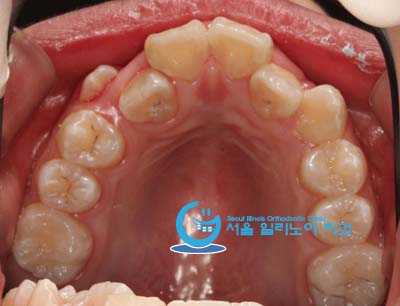

덧니교정9